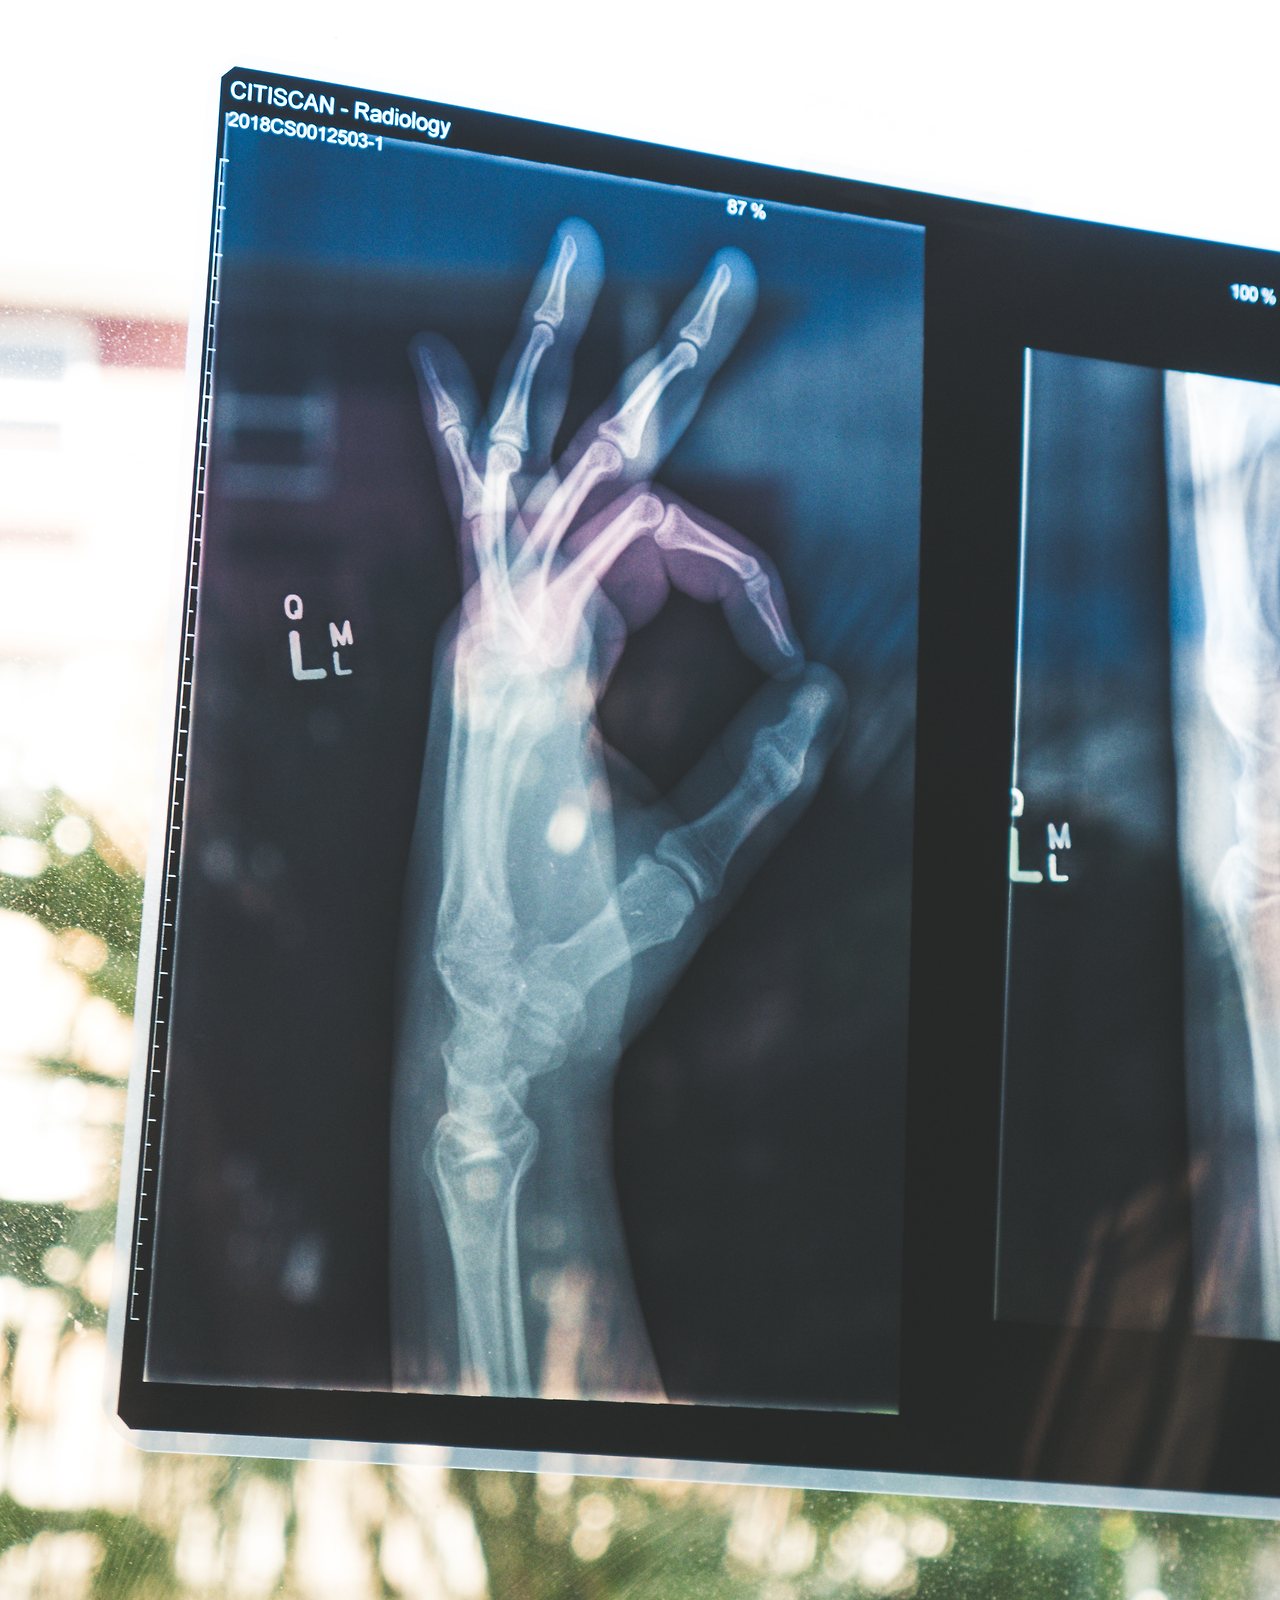

뼈에 구멍이 숭숭 뚫리는 건에 대하여

골밀도 검사를 권하시길래 정밀하게 검사를 했는데 수치가 좋지 않다.

조기폐경의 수순처럼 따라오는 질병이라 어느 정도 예상은 했지만

뼈에 구멍이 숭숭 뚫리는 속도를 늦추기 위해서 꼭 필요한 약이다.

뼈의 강도가 약해져서 골절이 일어나기 쉬운 상태가 되었다.

골밀도 검사에서 가장 취약한 부위의 수치가 나오는데 내 경우는 엉덩이뼈였다.